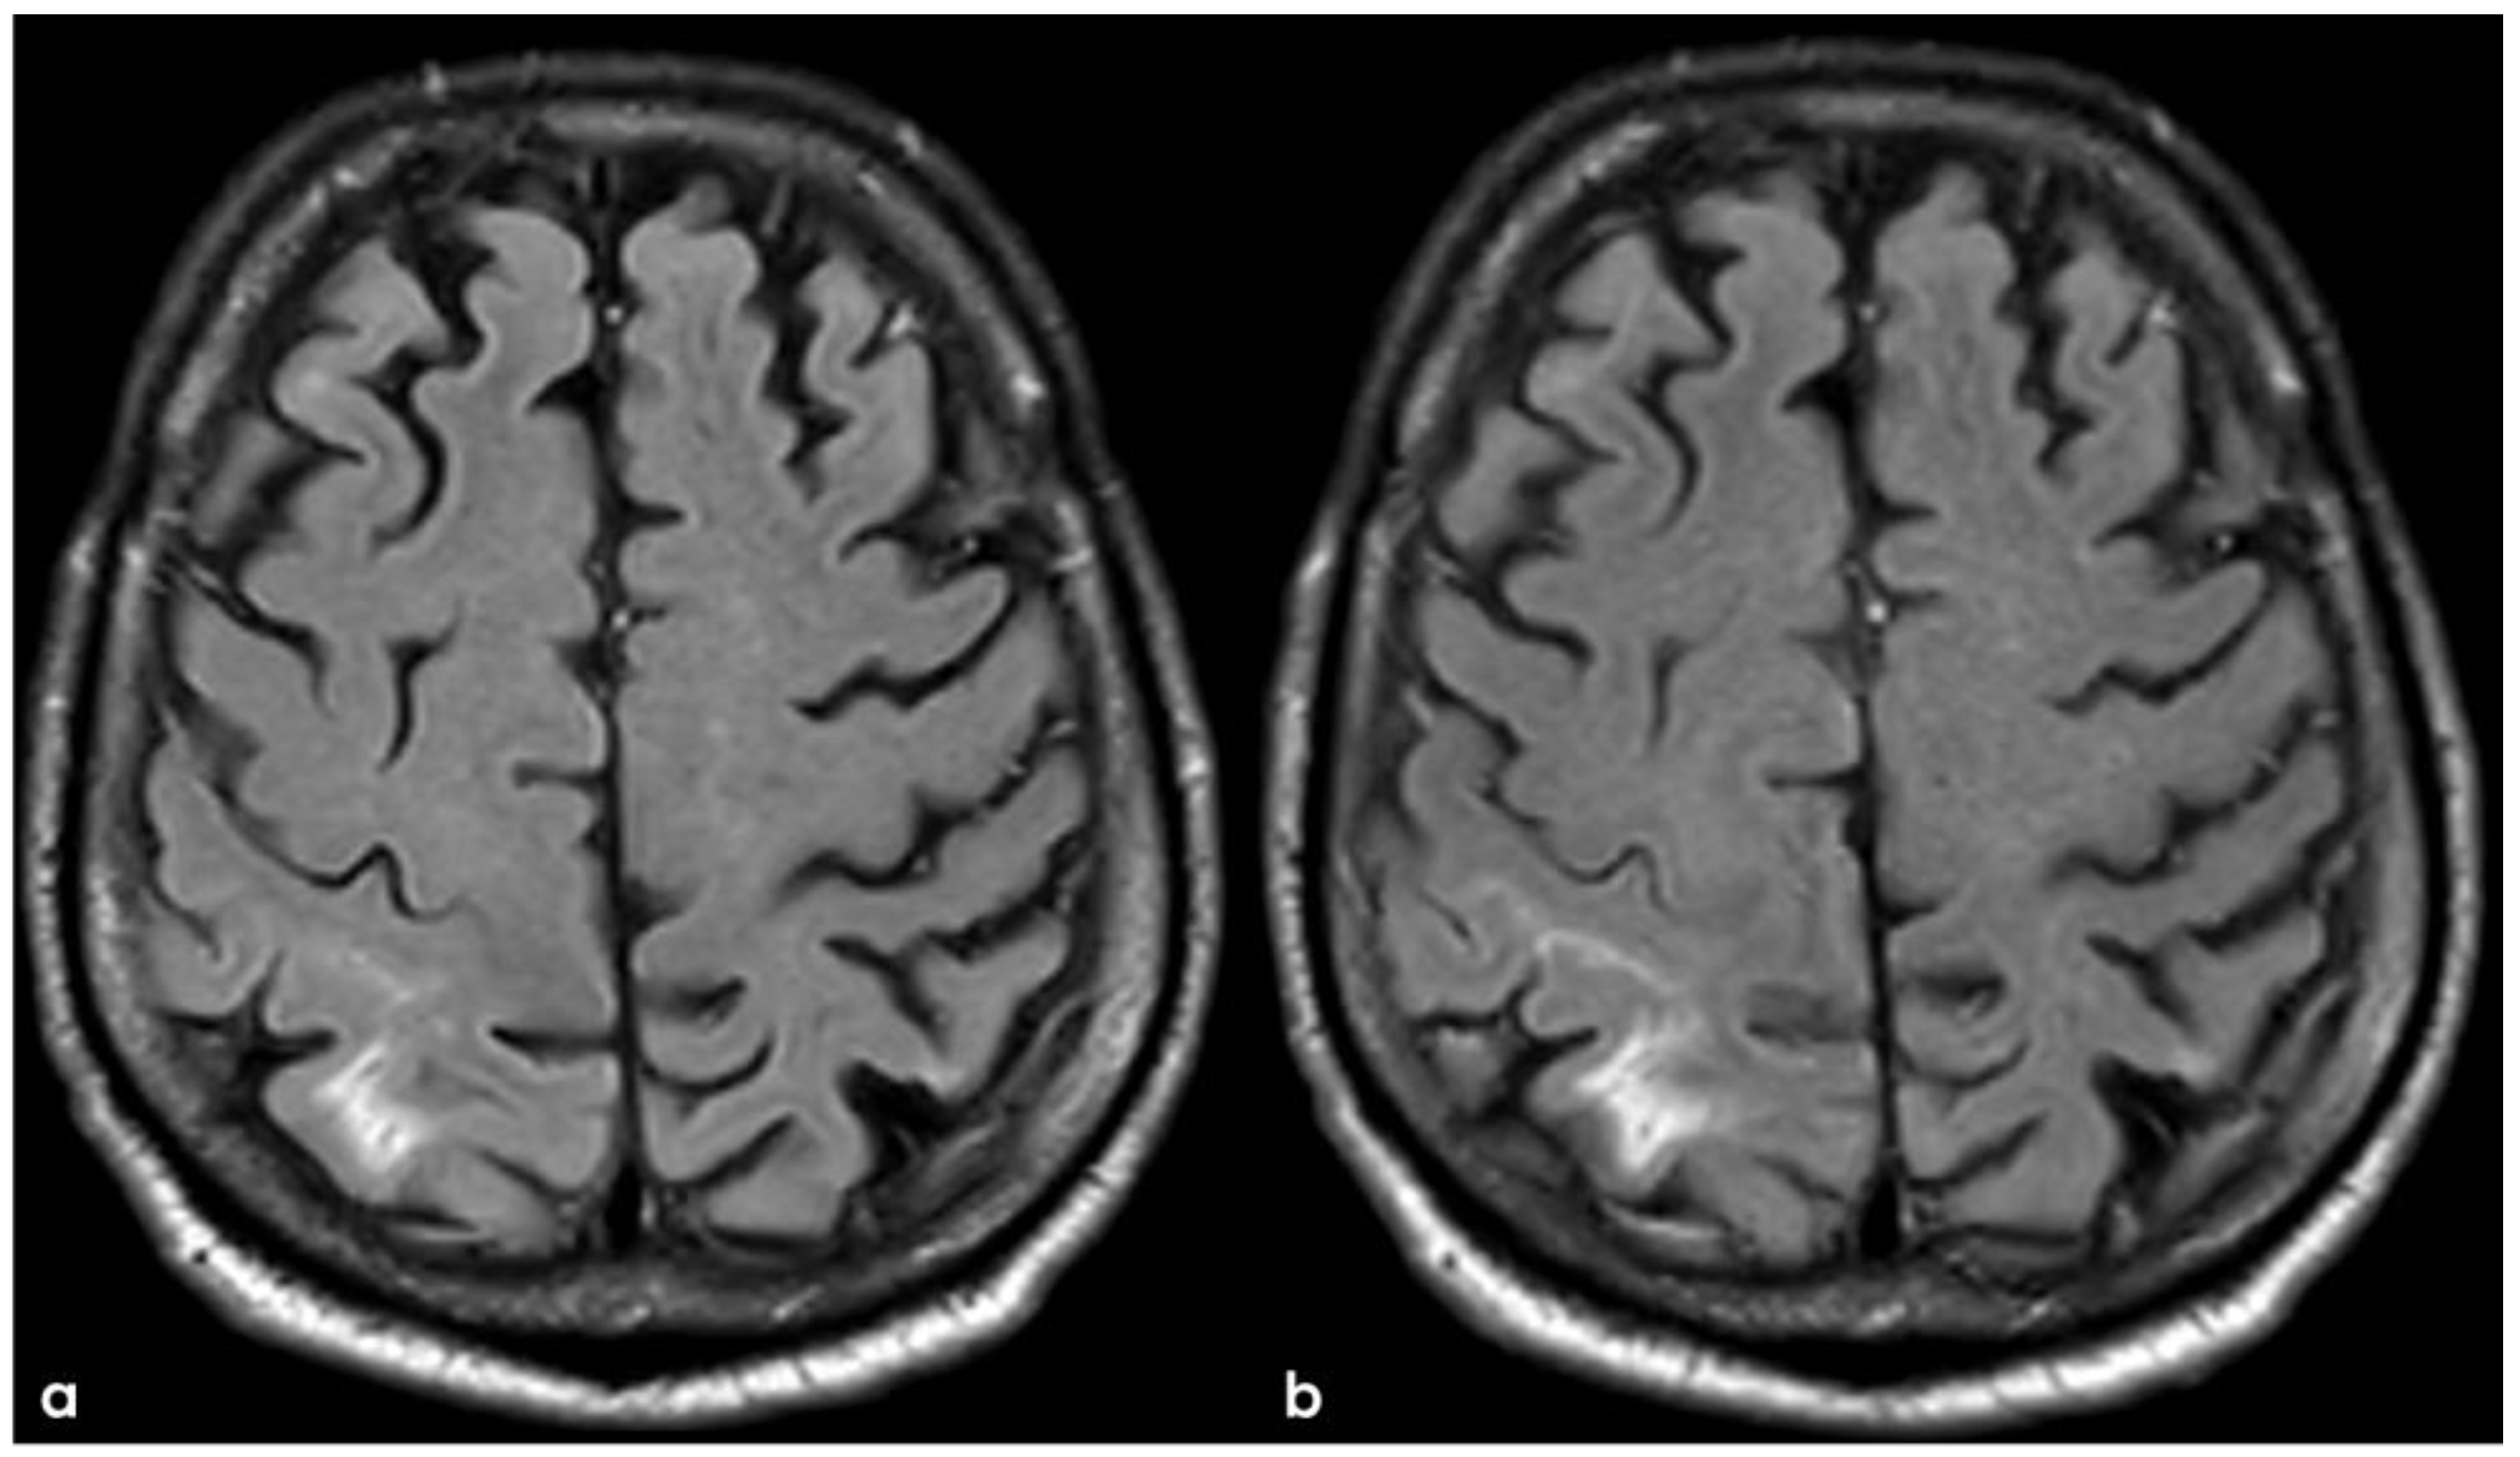

2. December 2013: Sulcal SAH and TFNEs